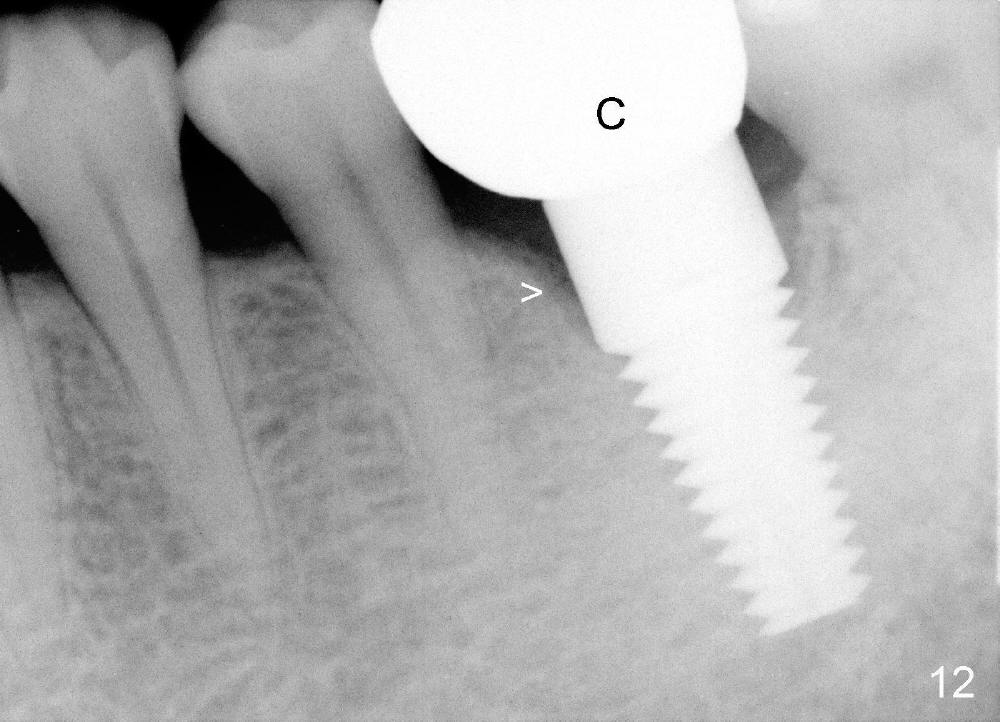

A 41-year-old man has discomfort in the lower left 1st molar. Exam shows swelling and a fistula in the mesiobuccal gingiva (Fig.1 >) and large radiolucency around the mesial root (Fig.2 *). After extraction and thorough debridement, osteotomy is initiated in the mesial socket, but the upper portion of the reamer (Fig.3 R, 2.5 mm) is placed in the middle of the edentulous space. By the time 5 mm reamer is removed, the osteotomy (Fig.4 O) forms mainly in the mesial socket with the septum (S) deviated to the distal socket. A 7x17 mm tap is placed with stability (Fig.5 T). An implant with the same dimension is placed with insertion torque more than 60 Ncm (Fig.6 I). With the large implant, two proximal sutures are able to close the remaining socket gaps (Fig.7). The swelling and fistula disappears and the gingiva tightly surrounds the implant in 1 week postop (Fig.8).

Two and a half months post cementation, the buccal metal show is much less and confined to the midbuccal portion. It appears that the papillae increase their mesiodistal dimension (data not shown). Bone appears to remain stable over the implant surface 2.5 and 9 months post cementation (Fig.12 >,13). The papillae around the implant crown remain normal 11 months post cementation (Fig.14 *). No bone loss is noticed 26 (Fig.15) or 38 (Fig.16) months post cementation. There is no bone loss around the 7x17 mm tissue-level implant 6 years 8 months post cementation (Fig.17).